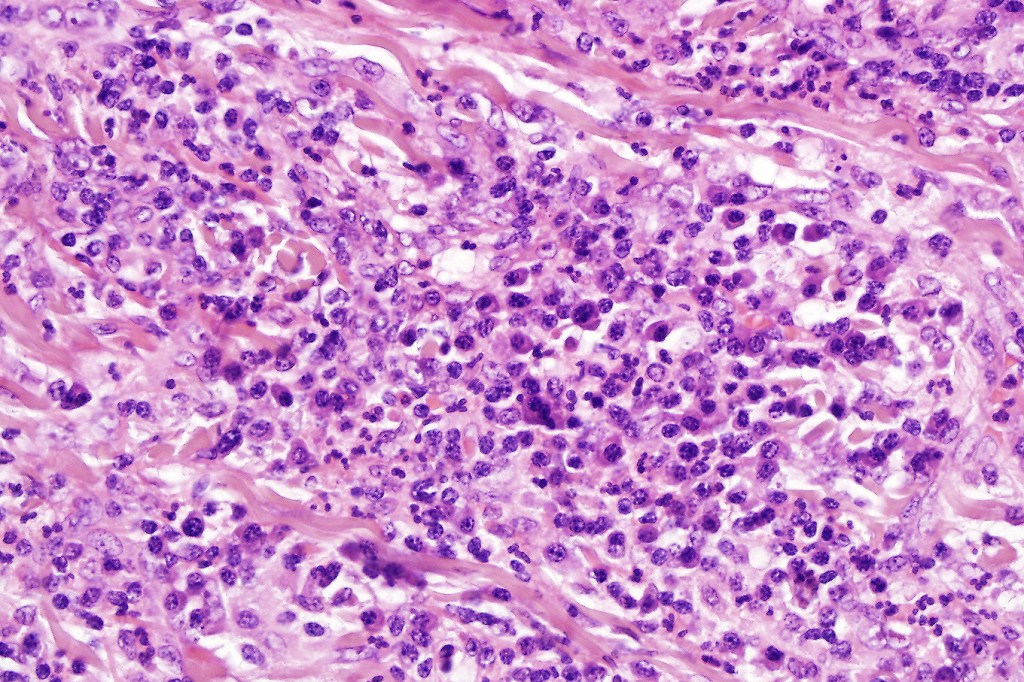

•Histiocytes are large with irregular borders and abundant cytoplasm

• Vesicular nuclei with a prominent nucleoli

•Emperipolesis of lymphocytes, plasma cells & neutrophils

•Background population of lymphocytes, plasma cells, neutrophils, eosinophils & variable numbers of xanthoma cells